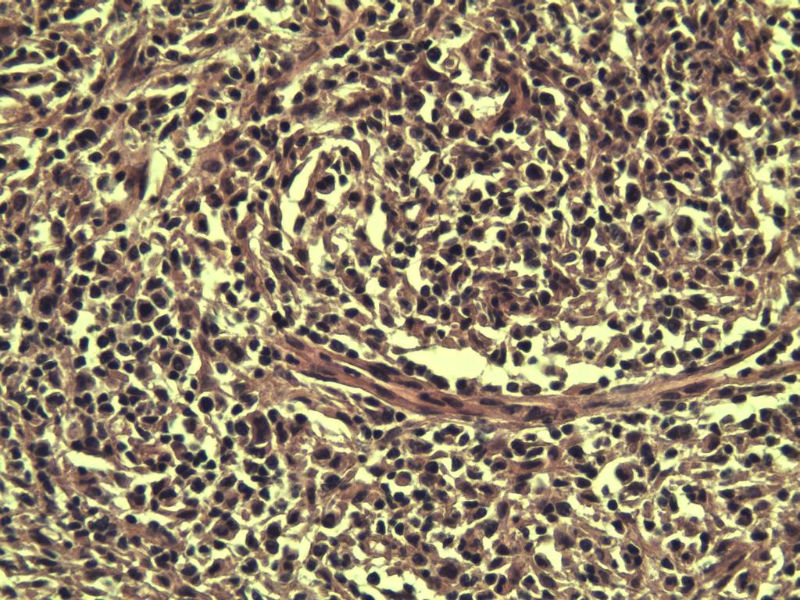

男,38岁,腹股沟 多枚淋巴结活检  直径 0.2-0.5 请各位老师看看 是什么 谢谢了!

"畏寒,发热咳嗽1年,加重伴腹部疼痛2月" 2月前患者感腹部疼痛不适伴大便呈稀大便,量不详,伴腰骶部疼痛,胸片:纵膈及右肺门多发性淋巴结肿大,进一步完善胸部CT:右肺及中叶病变,纵膈及肺门多发淋巴结肿大,结核性可能,脾脏增大,PPD(-),1个月来患者出现中上腹食欲不振,体重进行性消瘦,全身疲乏无力,3天前到医学院就诊,腹部B超:右肝囊肿,胆囊壁毛糙,脾大,胰周多个减弱回声,淋巴结不能除外,腹水,血常规示:WBC16.36x109 /L,N%14.25%,RBC2.63x1012/L ,HGB 66g/L 。右侧腋窝及腹股沟可扪及多枚淋巴结,压痛,无明显粘连。

腹股沟 多枚淋巴结活检图1

副皮质区增生,纤维化显著,细胞呈多形性,有一些多核巨细胞及一些异型细胞,病理性核分裂易见,胞浆红染,散在的小淋巴细胞,T细胞淋巴瘤不能除外,树突细胞肉瘤等鉴别。免疫标记。CD21、CD3、CD5、CD10、CD20、CD79a、PD1、CD68、CXCL13、KI-67、CD68、CD163等,据切片选择。不知对否。

淋巴结正常结构破坏,可见大的异型细胞,上皮样或梭形,恶性肿瘤,依据病史,首先考虑淋巴造血系统疾病,大中小细胞混杂,大细胞多,形态多样,可见多核瘤细胞,除以上考虑外需鉴别间变大、组织细胞肉瘤、指状突/树突细胞肿瘤、HL等,还需排除肉瘤或癌转移,尽管病人年轻,加上ALK、CK、S-100、CD1a。